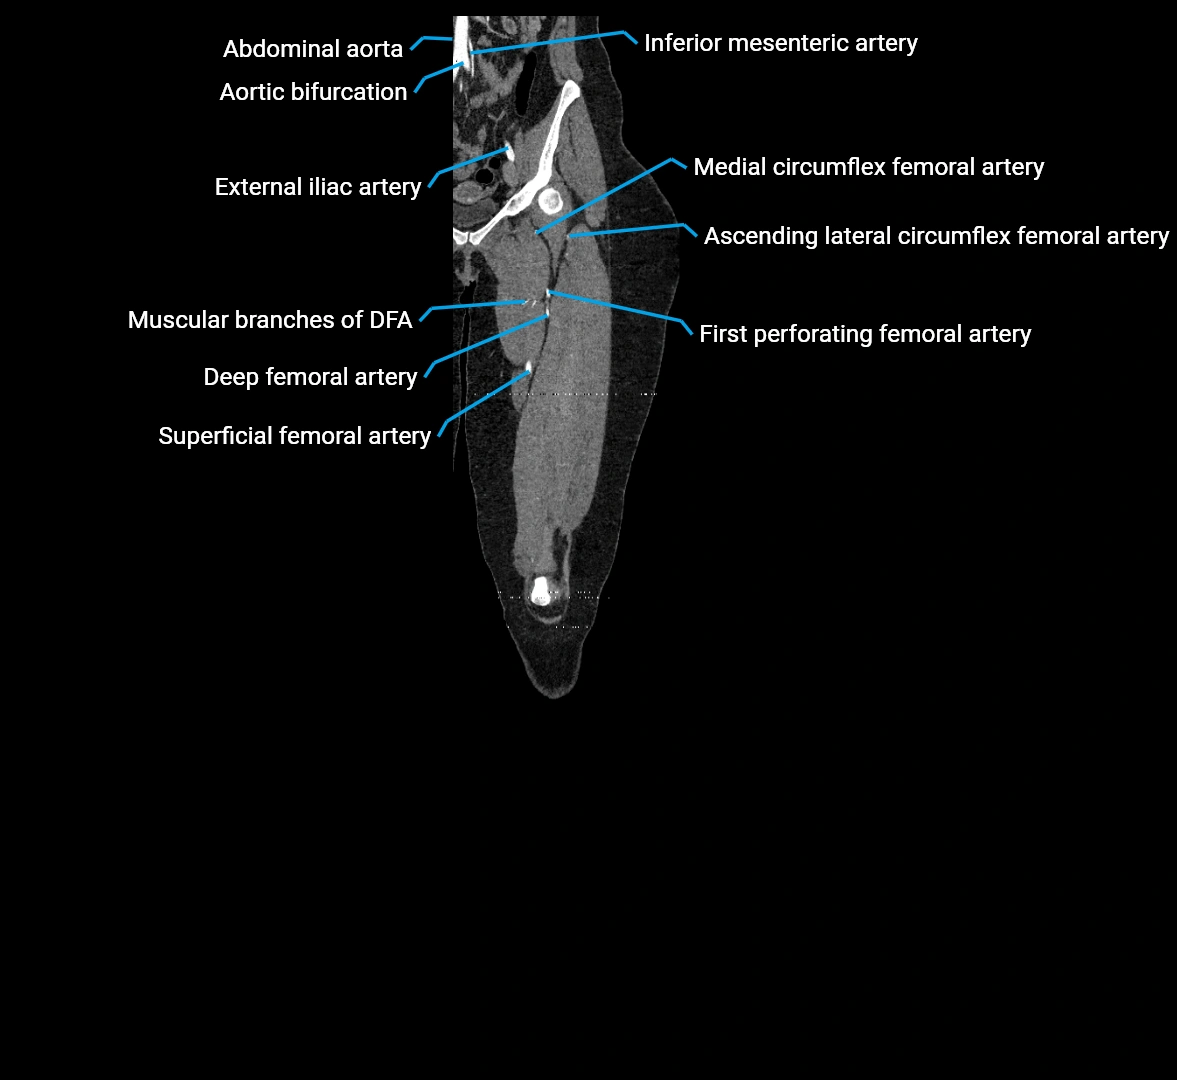

CT images

image

Contrast-enhanced CT (CTA):

• Gold standard for abdominal aortic imaging

• Provides excellent detail of lumen, wall, aneurysm, thrombus, and branch vessels

• Multiplanar and 3D reconstructions help in aneurysm measurement, stent graft planning, and dissection evaluation